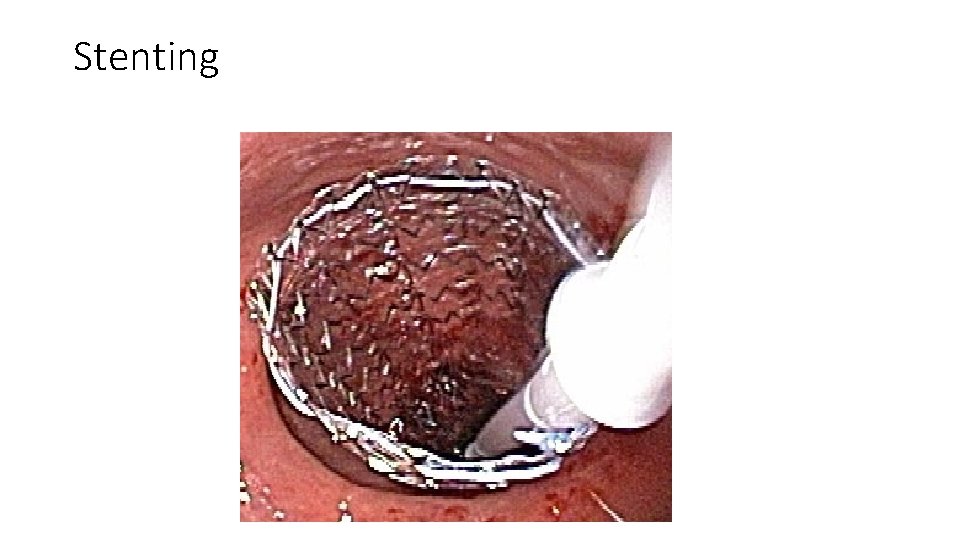

Left colon carcinoma • Surgical treatment of left colon carcinoma includes 1. resection without primary anastomosis 2. resection with primary anastomosis and intraoperative lavage • Endoscopically placed expandable metal stents can be used to relieve the large-bowel obstruction, thus allowing for a primary colorectal anastomosis

Stenting

Right colon cancer • Right colectomy and a primary anastomosis between the ileum and the transverse colon. • Patients with high-risk features for surgery (advanced age, complete obstruction, or severe comorbidities) may benefit from stent placement until the patient can be optimized for a surgical procedure • Palliative colorectal stents are an option in patients who are poor surgical candidates or have advanced cancer.